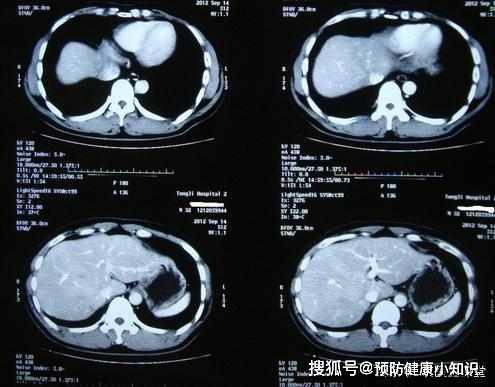

結果肝臟CT有明顯占位,轉氨酶升高,甲胎蛋白也高到了810,確診為肝癌,由於癌細胞已經擴散,病情已經發展到了晚期。